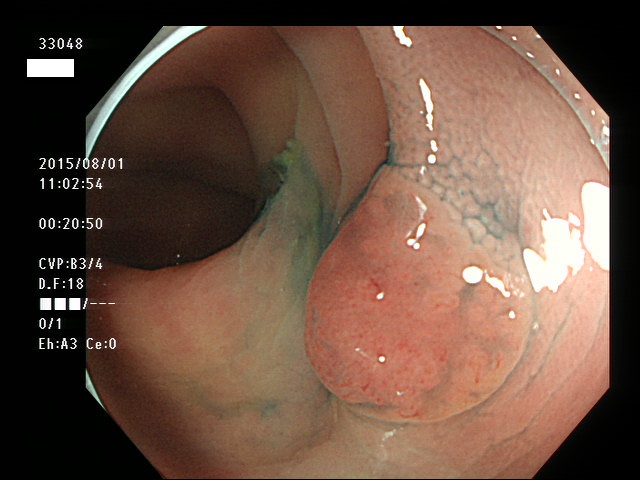

上記100名より抽出した平坦・陥凹型腺腫(=癌化の危険が高いが見落としやすい病変)の内視鏡写真

33003 33004 33005 33006 33007 33008 33009 33010 33011 33012 33013 33014 33015 13306 33018 33021 33024 33025 33026 33029 33030 33031 33032 33033 33036 33038 33039 33041 33042 33045 33046 33048 33051 33053 33054 33055 33057 33060 33063 33066 33068 33069 33071 33072 33074 33077 33078 33080 33086 33088 33089 33090 33091 33093 33095 33096 ・・・・・・の56名